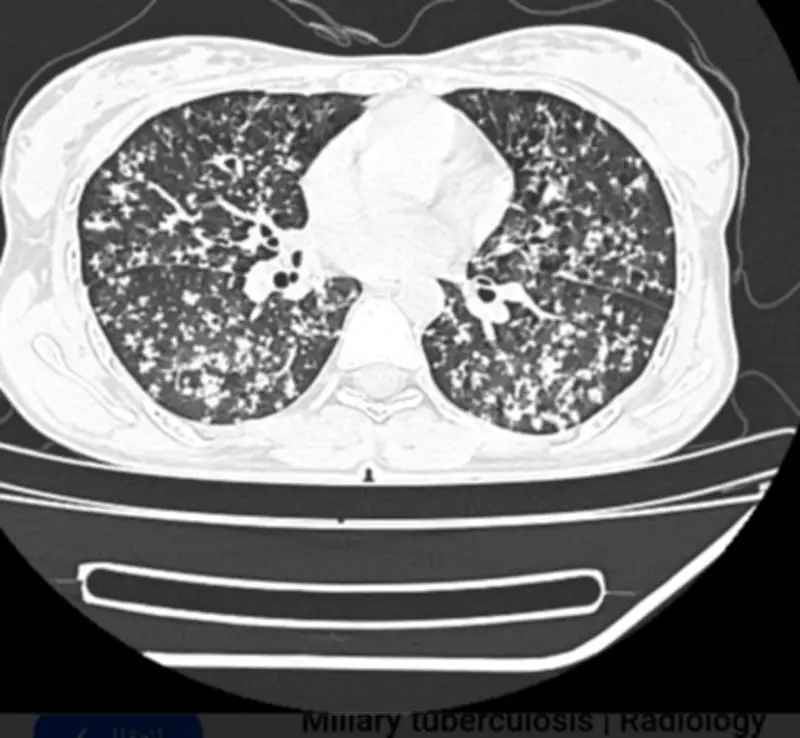

في إنجاز طبي بارز، تمكن فريق طبي متخصص في مستشفى المانع العام بمدينة الأحساء من إنقاذ حياة مريض كان يعاني من حالة صحية خطيرة، حيث تم تشخيص إصابته بمرض السل الرئوي المنتشر، مصحوباً بنقص حاد في مستويات الأكسجين في الدم.

وصل المريض إلى المستشفى وهو في وضع صحي حرج، مع أعراض تشير إلى ضيق شديد في التنفس وارتفاع في درجة الحرارة. وبفضل الكفاءة العالية للفريق الطبي، تم إجراء الفحوصات اللازمة على الفور، والتي كشفت عن انتشار العدوى الرئوية ونقص الأكسجين الحاد.